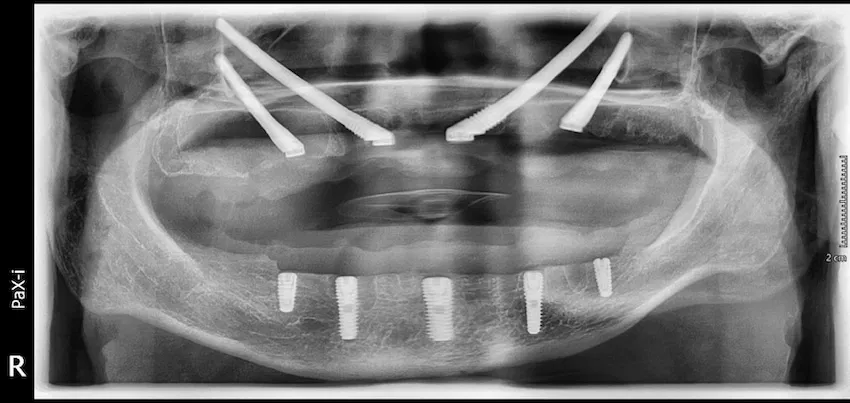

An X-ray of All-on-X dental implants shows every detail of the analysis of the bones and the place where the implants were put. This step of the diagnosing process is what ensures the ideal positioning with the greatest stability and that the foundation for a secure, durable, full-arch prosthesis has been formed.